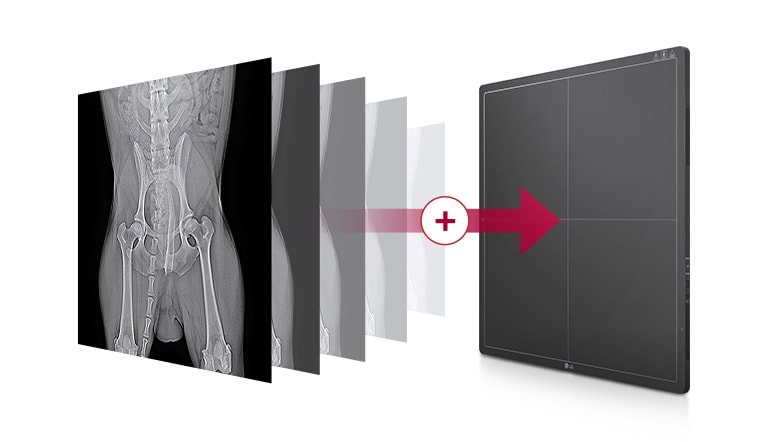

Capteur plan 17x17"

Amélioration de l'efficacité du travail

Disponibilité rapide des images

Disponibilité de l’image brute en 2 secondes avec une connexion filaire, ou 2,5 secondes avec une connexion sans fil